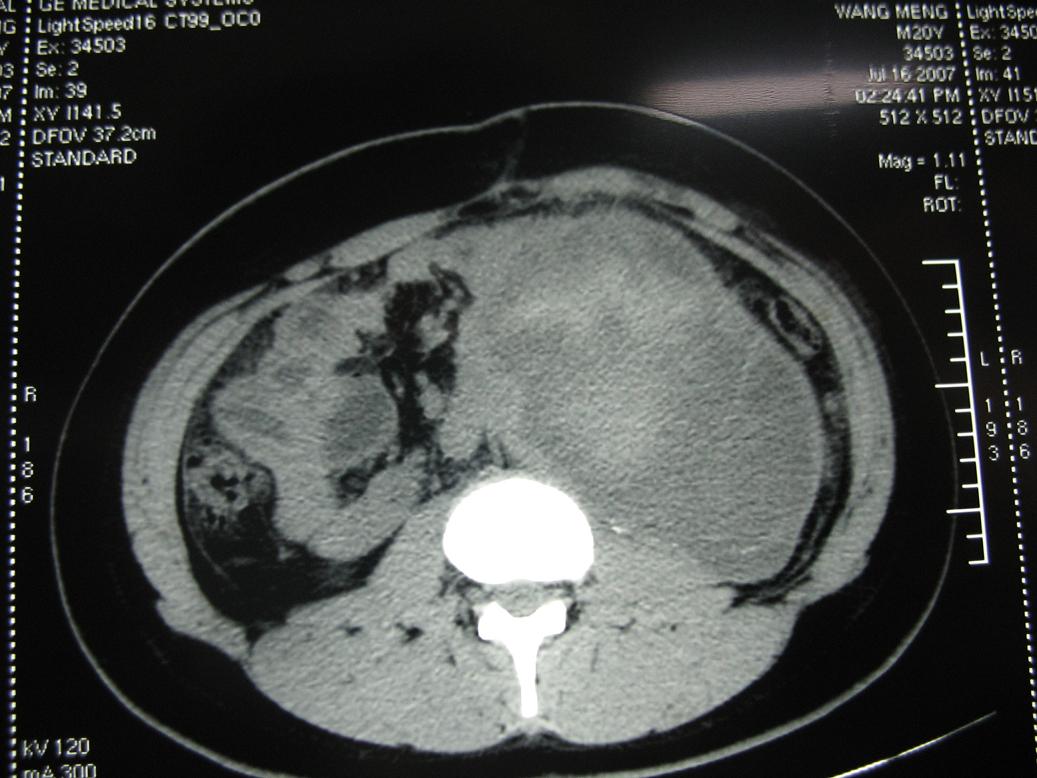

1)考虑左侧腹膜后恶性肿瘤(肉瘤?)伴瘤体内出血。2)左肾积水。

他的前腹壁脂肪组织内,怎么会有条形的略高密度影,那是什么???